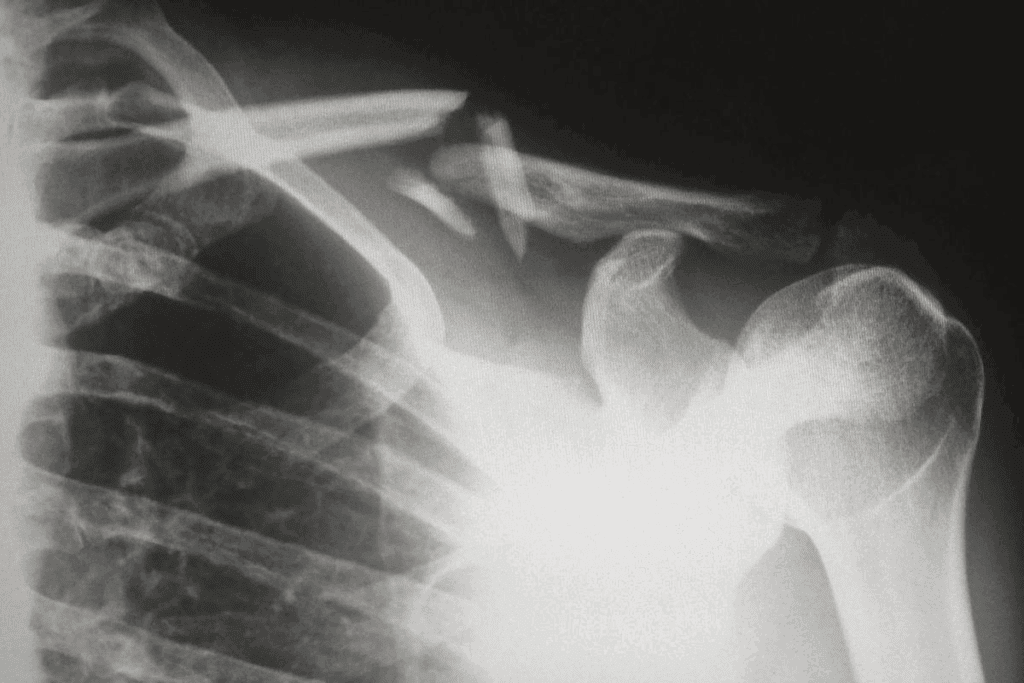

Initial Assessment and Diagnosis

The first step is a careful check-up and diagnosis. We look at the patient’s medical history, do a physical exam, and use X-rays, CT scans, or MRI to see how bad the injury is.